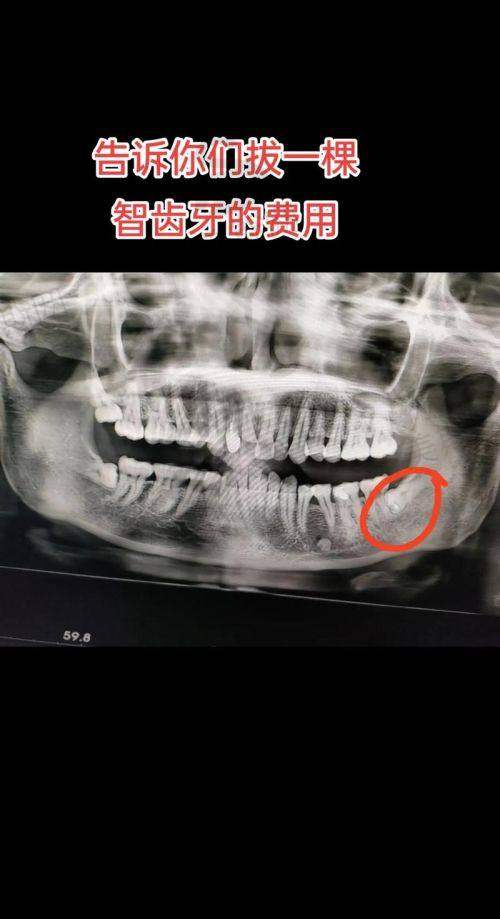

6. 口腔综合治疗:涵盖洗牙(超声波洁牙 + 喷砂抛光)、补牙(树脂充填、玻璃离子充填)、拔智齿(微创拔除阻生齿)、根管治疗等基础项目,医疗保险报销比例达50%-80%。

10. 微创拔智齿(上颌):300元/颗起,不含复杂阻生齿

11. 微创拔智齿(下颌):800元/颗起,含局部麻醉